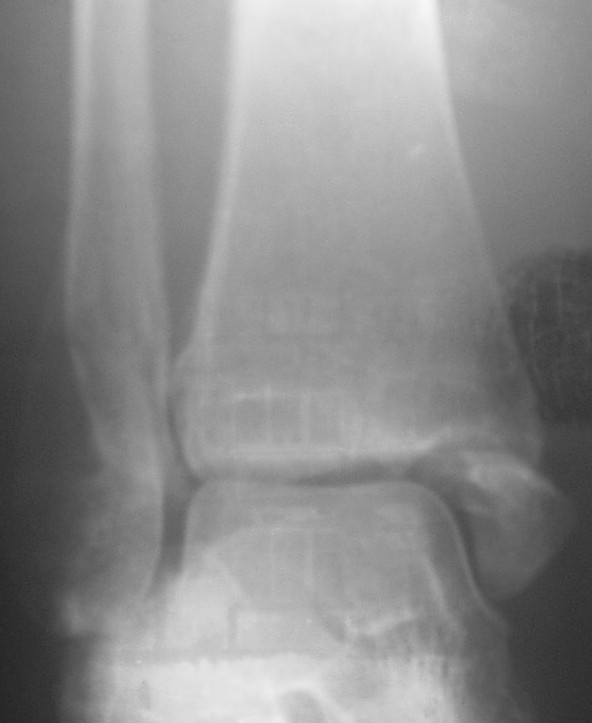

Трехчетвертной

На боковом довольно неплохой сустав, скудная информация о положении вилки сустава при косой рентгенограмме (Mortise view) из-за положения стопы во внутренней ротации и эквинуса во время ренгенограммы.

Мне кажется это тень внутренней лодыжки, которая находится в положении сгибания (flexion), т.е. указывающее на неправильно сросшийся или несросшийся перелом.

На прямом снимке наружная лодыжка немного укорочена и по описанию на КТ синдесмоз расширен.

На представленных снимках с исправлением, нейтральное положение стопы во время рентгенограммы, укорочение малоберцовой не менее 4-5 мм и ротация, смещенная и ротированная внутренняя лодыжка.